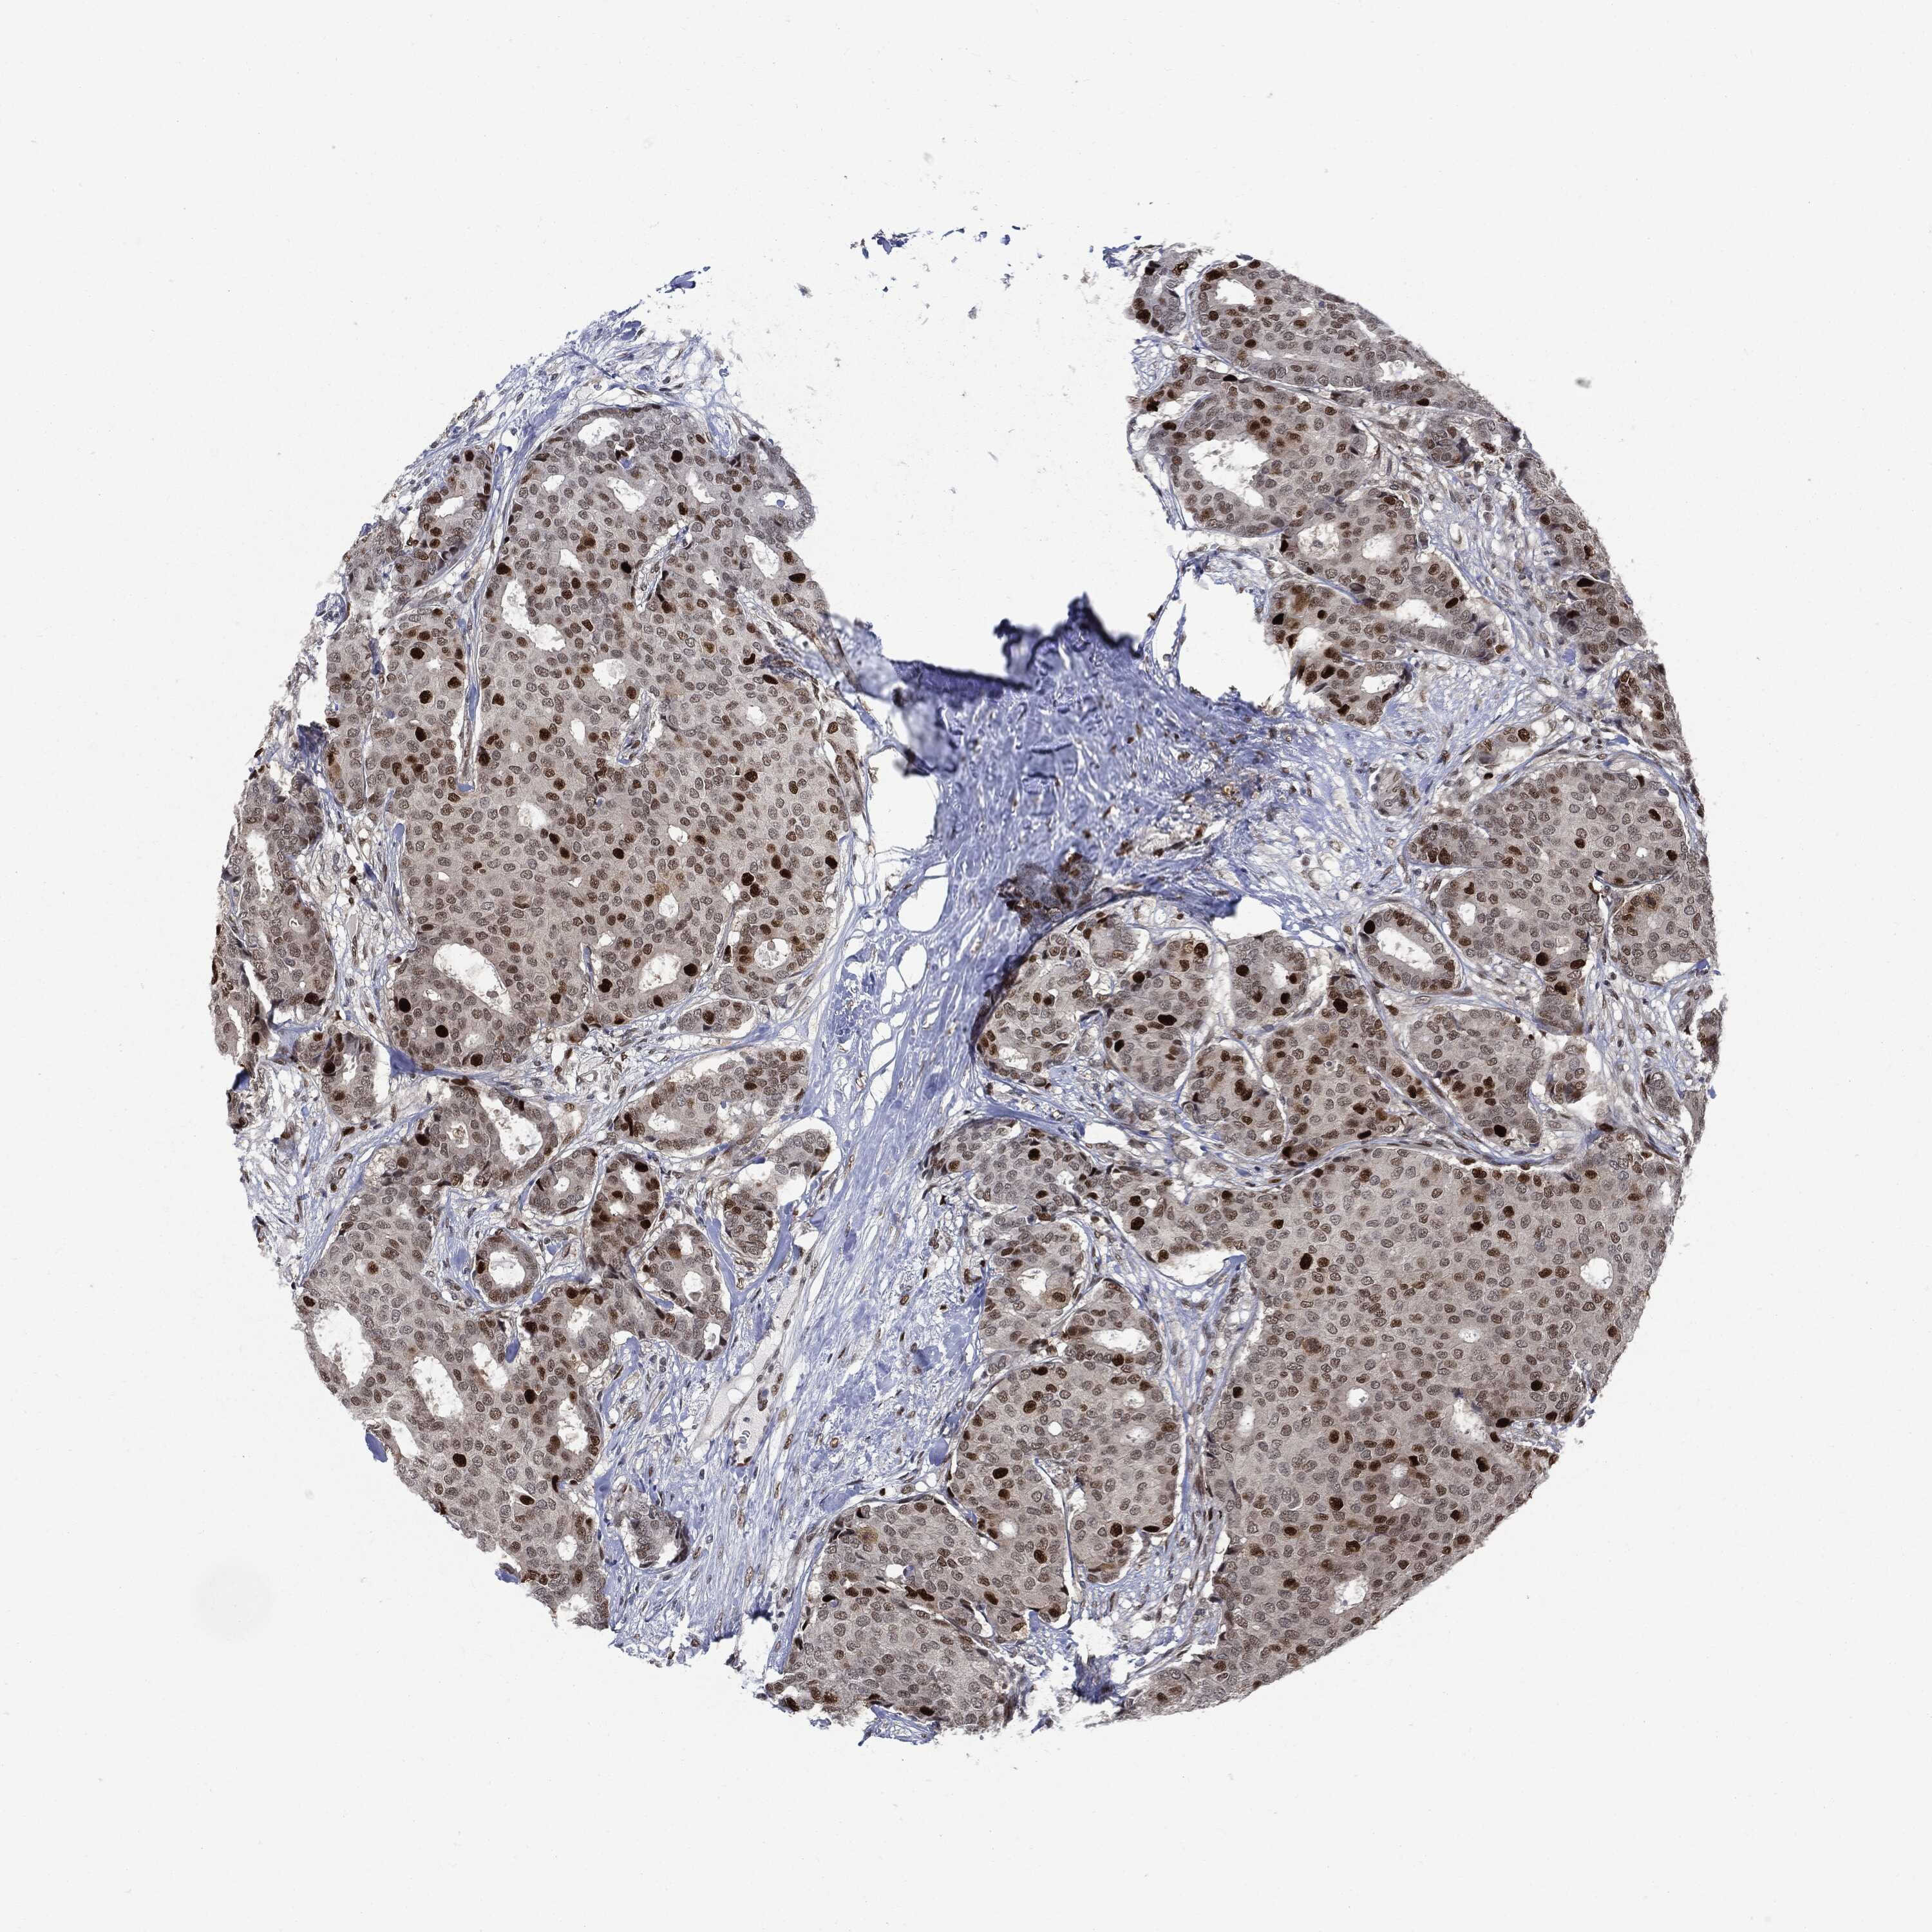

CANCER BREAST CANCER Show tissue menu

BRCA TCGA BRCA VALIDATION PROTEIN EXPRESSION

ANTIBODIES

AND

VALIDATION